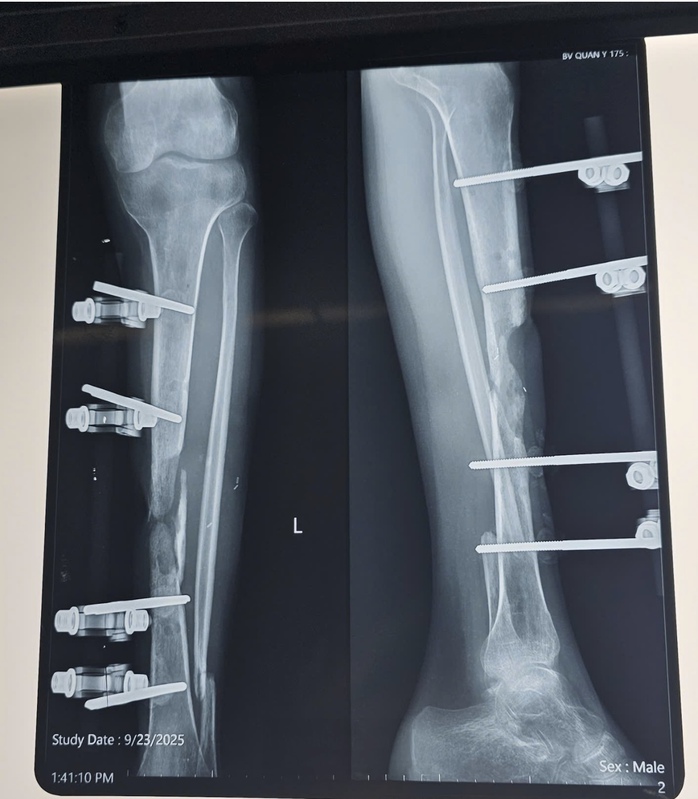

Ngày 23-9, anh L. nhập viện vào Khoa Bỏng và Vi phẫu tạo hình-Viện Chấn thương Chỉnh hình (Bệnh viện Quân y 175) trong tình trạng bị sẹo mổ cũ vùng trước xương chày xơ dính, còn khung cố định ngoài, khuyết xương chày khoảng 8 cm, gãy cũ xương mác trái, chân trái ngắn hơn chân phải khoảng 2 cm, không còn biểu hiện viêm hay nhiễm trùng.

Hình ảnh cho thấy bệnh nhân bị khuyết xương chày cẳng chân trái sau viêm xương tủy xương do gãy hở hai xương cẳng chân trái.

Sau thăm khám và hội chẩn, bệnh nhân được chẩn đoán: Khuyết xương chày cẳng chân trái sau viêm xương tủy xương do gãy hở hai xương cẳng chân trái năm thứ 2, còn khung cố định ngoài cẳng chân trái.

Bệnh nhân được phẫu thuật cắt bỏ đoạn xương viêm, làm mới ổ gãy; chuyển phức hợp vạt da xương mác tự do từ chân đối diện nối vào bó mạch chày trước cẳng chân trái bằng kỹ thuật vi phẫu, kết hợp xương bằng nẹp vít.

Sau 14 ngày phẫu thuật, vạt da hồng hào, siêu âm tại vùng nhận vạt mạch máu lưu thông tốt, đảm bảo vạt sống 100%, hình ảnh X-quang cho thấy xương thẳng trục, chiều dài 2 chân bằng nhau. Bệnh nhân hồi phục tốt, sinh hoạt bình thường, không có biến chứng sau mổ.